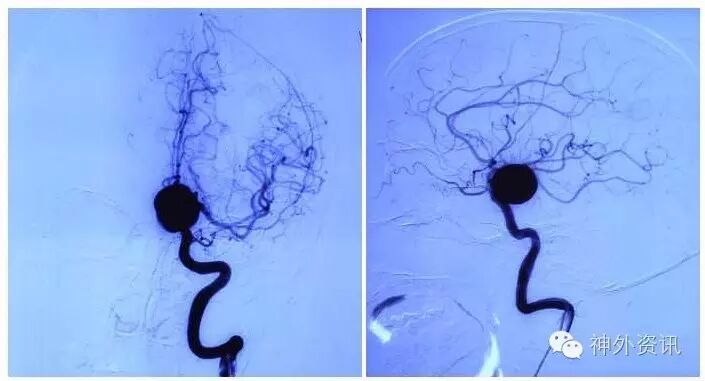

《床突上段大动脉瘤》